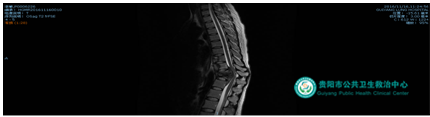

病例1:病人是由省級醫(yī)院轉(zhuǎn)診的腰椎結(jié)核患者,腰痛明顯,行走時(shí)感下肢麻木;腰4、5椎體破壞,尤其腰4椎體僅剩0.3cm厚,單純填塞骨頭支撐力度不夠,手術(shù)時(shí)采用鈦籠植骨支撐,但后路脊柱手術(shù)開窗小,放置鈦籠難度大,經(jīng)過精心設(shè)計(jì)成功從后路完成鈦籠放置。

術(shù)前